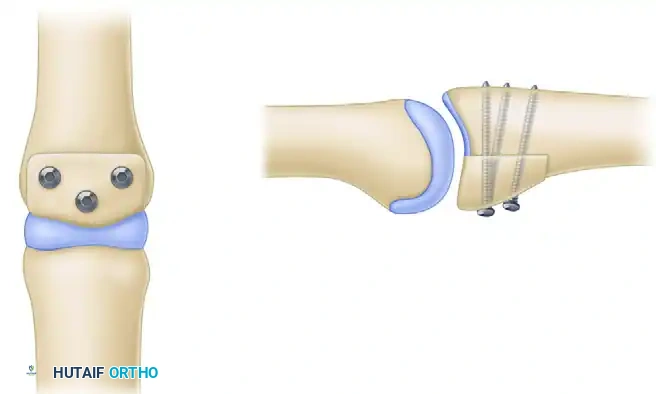

- Definitive Fixation: Fix the graft rigidly in place using two or three 1.0-mm to 1.5-mm screws directed from volar to dorsal. The screws should be placed in lag fashion to compress the graft into the host bone bed. A third screw can be placed in the hole left by the provisional K-wire if the graft size permits.

Volar view of the PIP joint demonstrating the hemi-hamate graft secured with three interfragmentary screws.

Lateral view of the PIP joint showing the inset graft reconstituting the articular concavity and the volar lip.

Detail of the 1.0 mm or 1.3 mm screws placed through the hamate graft.